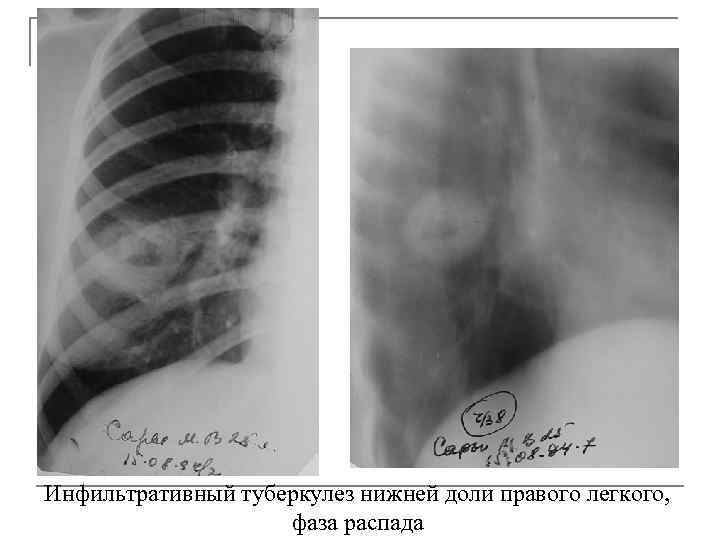

Симптомы и лечение инфильтративного туберкулеза легких

Раздел: Снимки-откровения